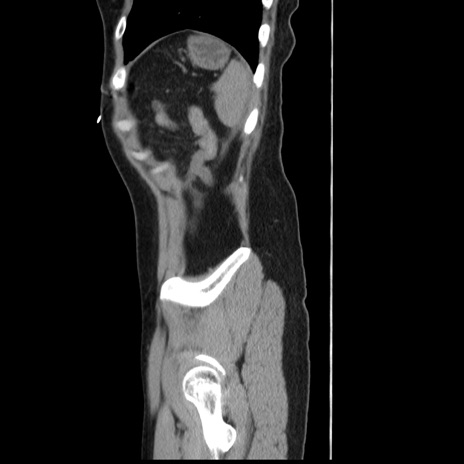

症例10(矢状断像)

【症例】 50歳代女性

【主訴】 腹痛

【現病歴】前日生レバーを食べた。今朝に排便あり。 昼前に突然発症の腹痛を生じ、当院救急外来を受診した。

【既往歴】 子宮筋腫にてで子宮全摘後

【身体所見】 意識清明、腹部:平坦、軟、下腹部やや左を中心に圧痛・反跳痛あり、筋性防御あり

【データ】WBC 7800、CRP 0.07